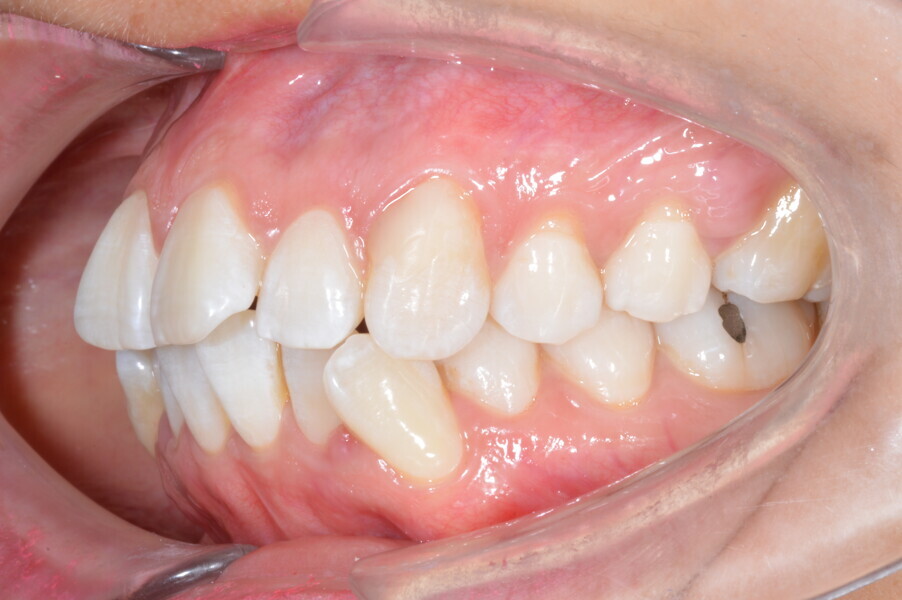

A 35-year-old female patient presented with crowding, muscle and joint pain, and headaches upon awakening. Examination found a skeletal Class I with crowding and bimaxillary protrusion. Facial examination showed a convex profile with protruded lips and a square face shape, intensified on smiling (Figs. 1–4). She reported bruxism, and bilateral masseteric hypertrophy was observed, but there was no alteration of the temporomandibular joints.

Before the aligner treatment began, the maxillary and mandibular second premolars were extracted to create space. With orthodontic treatment, distalisation of the anterior teeth was achieved by employing maximum mandibular anchorage and moderate maxillary anchorage (Figs. 5–7). At the end of the treatment, a stable bilateral Class I occlusion had been achieved, as well as normal inclination and retrusion of the anterior teeth, consequently improving the profile (Figs. 8–10).